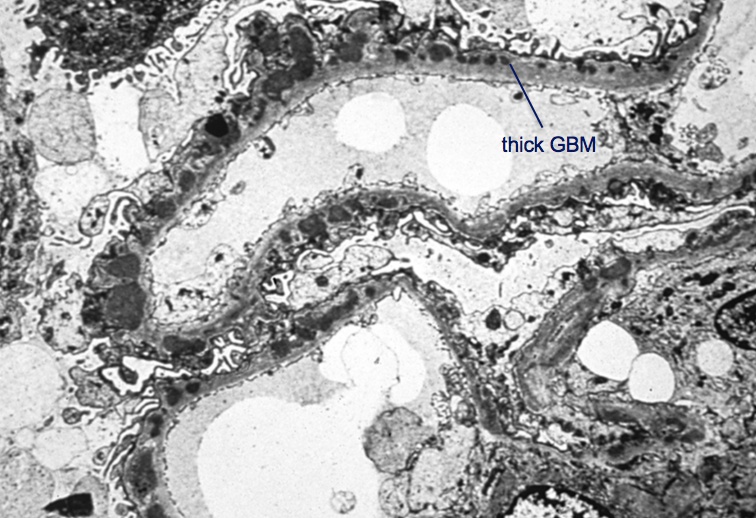

thick GBM

Spike and Dome

no triggering inflammation

Membranous Nephropathy